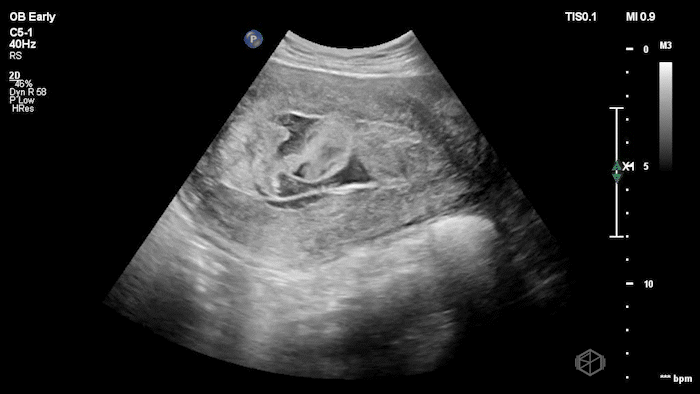

04 - What is the most likely diagnosis and definitive next step for this patient?

Left adnexal complex mass with significant free fluid concerning for ruptured ectopic pregnancy (OB Early setting).